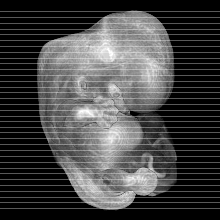

MRI Slice Selector

Mouse: click on a line below to select a view

Finger: tap a line below with a very light touch